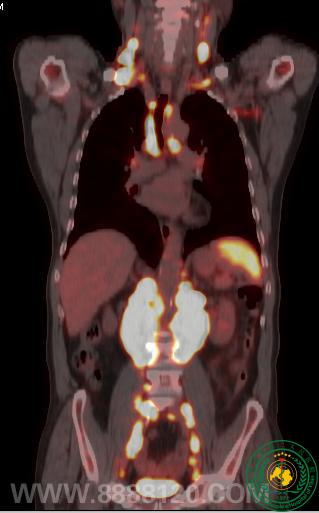

我院分子影像设备PET/CT的引进,填补宜宾空白,提升宜宾影像技术新台阶

我院分子影像设备PET/CT的引进,填补宜宾空白,提升宜宾影像技术新台阶36925